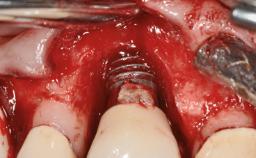

Peri-implantitis Treated with Access-Flap Surgery

A 27-year-old male was referred to the periodontist for assessment and management of implant site 41. The implant had been placed nine years previously and restored with a screw-retained single crown. The patient was a cigarette smoker in good general health. He reported he had reduced his smoking habit from 25 cigarettes per day to 15 cigarettes per day in the previous six months. On examination, there was calculus and plaque present at the lower anterior teeth and at implant site 41. Localized attachment loss was observed at teeth 32 and 42, with 2–3 mm of gingival recession. At implant site 41, there were 8–9 mm probing depths with suppuration and bleeding on probing.